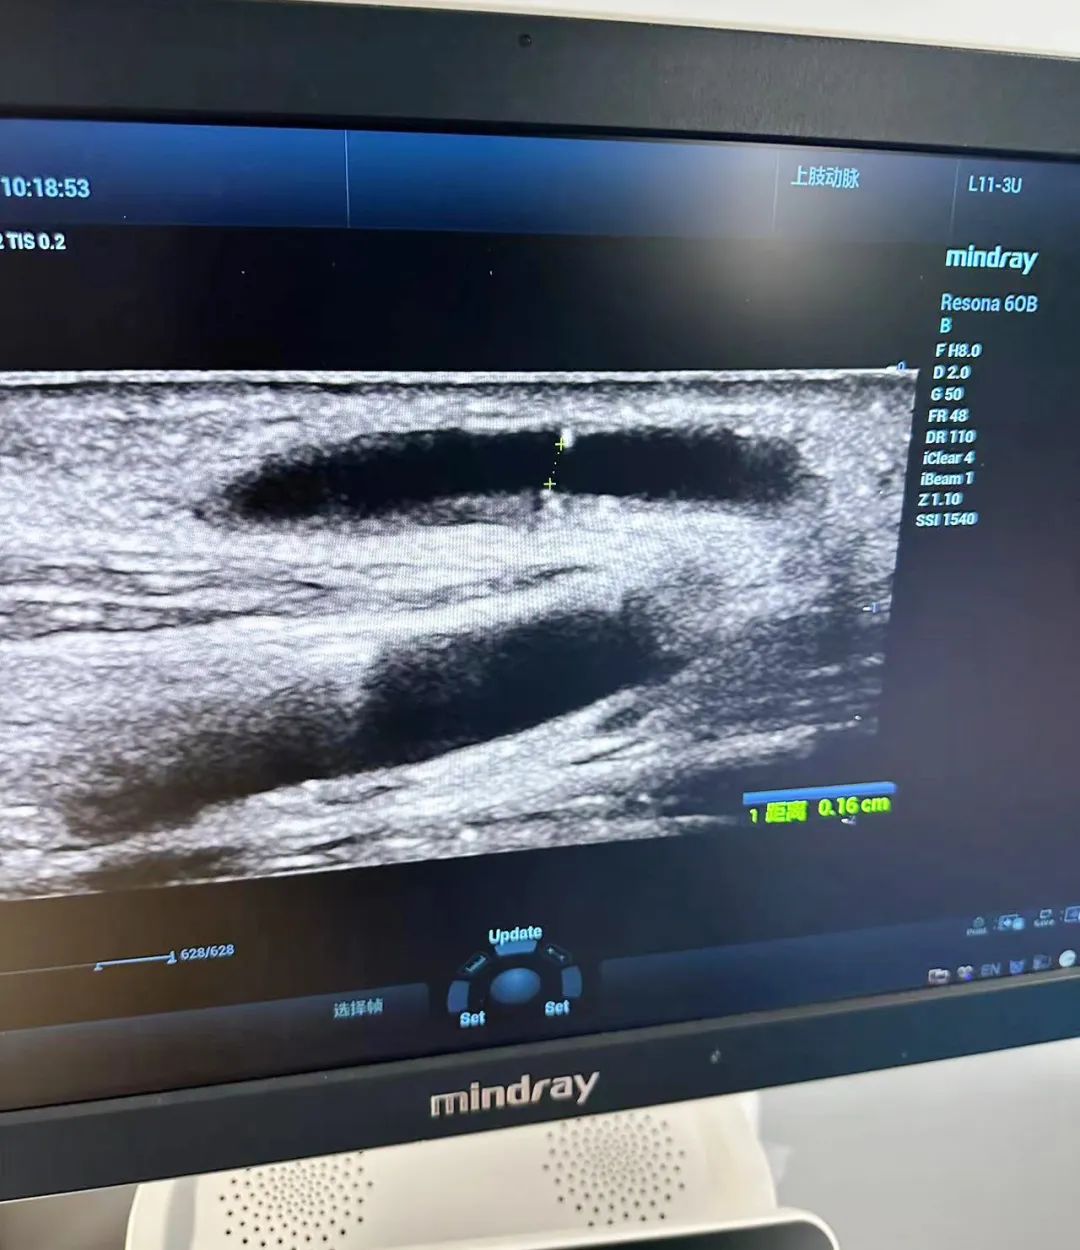

交流會結(jié)束后,血透中心與彩超室通力合作,為多名血透患者進行了血管B超檢查。通過篩查,發(fā)現(xiàn)了一些患者血管通路出現(xiàn)問題,并及時指導(dǎo)他們進行血管通路干預(yù),以避免內(nèi)瘺的風(fēng)險。同時,李教授對內(nèi)瘺評估及血流量測量,內(nèi)瘺穿刺等內(nèi)容進行細致講解,這一舉措有效提高了醫(yī)生對動靜內(nèi)瘺評估的能力,提升了護士動靜脈內(nèi)瘺彩超穿刺技術(shù)的水平,得到了醫(yī)患雙方的一致好評。